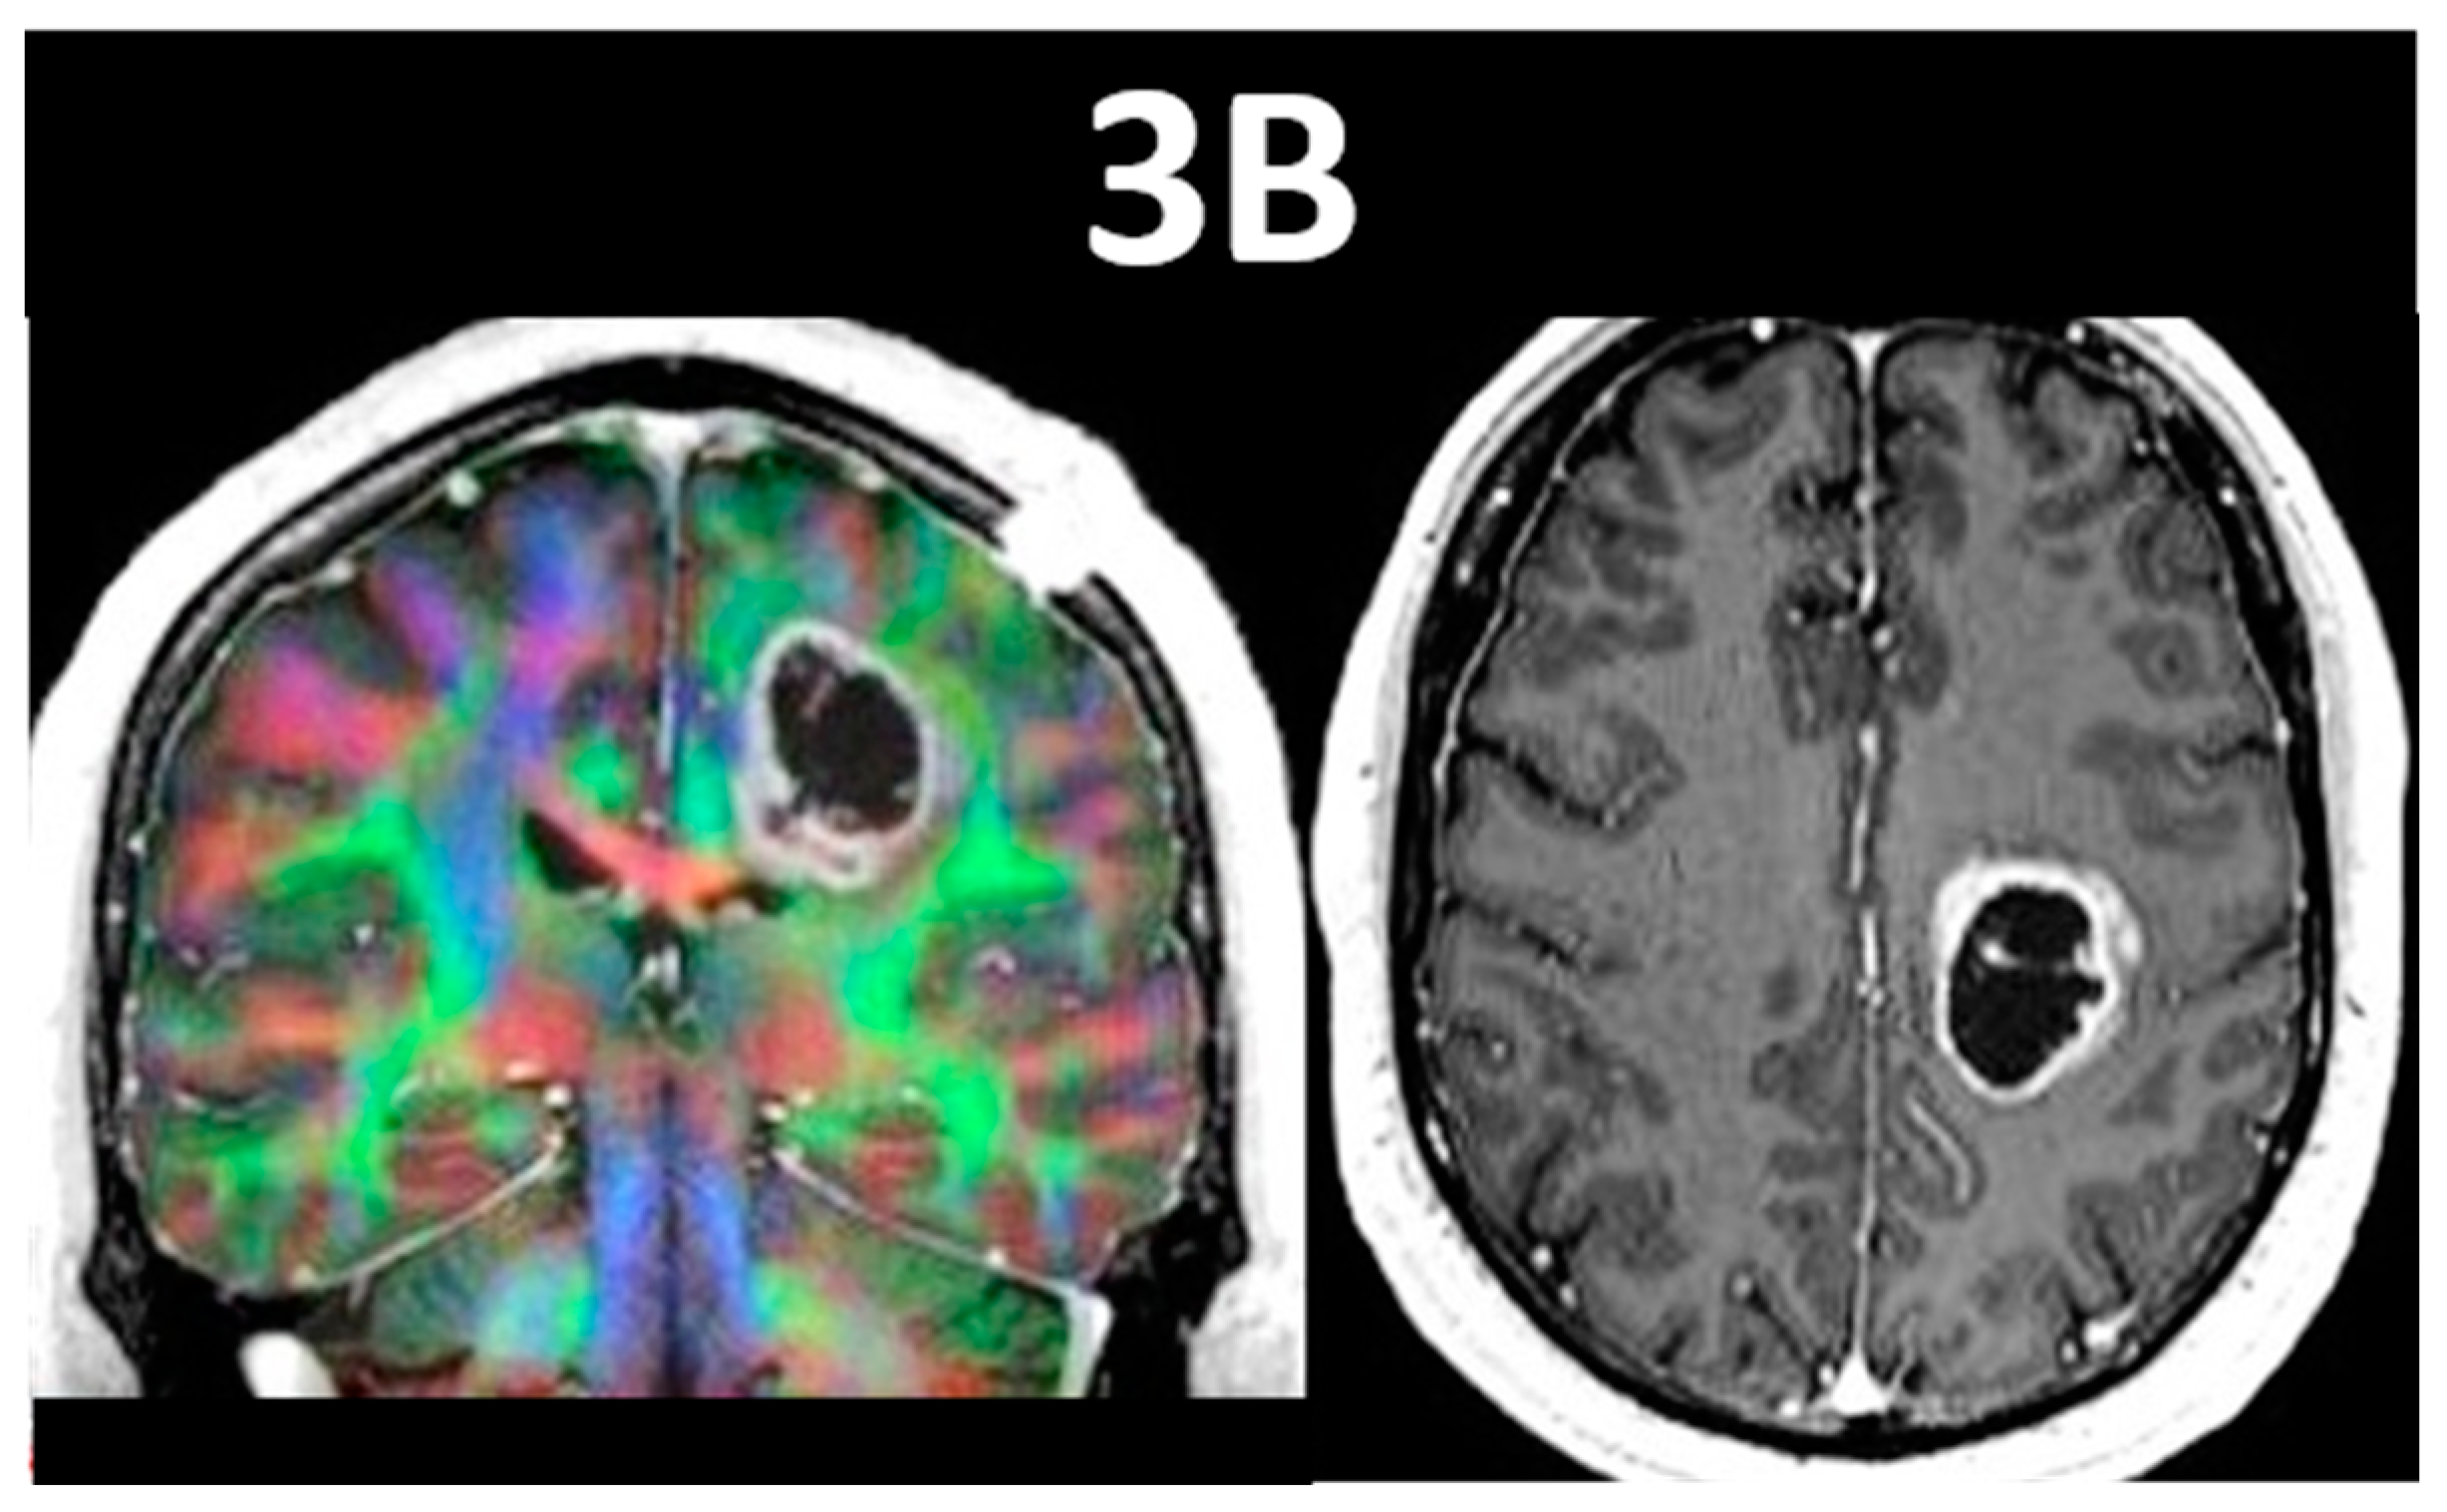

- Pillai, J.J.; Zaca, D. Comparison of BOLD cerebrovascular reactivity mapping and DSC MR perfusion imaging for prediction of neurovascular uncoupling potential in brain tumors. Technol. Cancer Res. Treat. 2012, 11, 361–374. [Google Scholar] [CrossRef]

- Zaca, D.; Jovicich, J.; Nadar, S.R.; Voyvodic, J.T.; Pillai, J.J. Cerebrovascular reactivity mapping in patients with low grade gliomas undergoing presurgical sensorimotor mapping with BOLD fMRI. J. Magn. Reson. Imaging 2014, 40, 383–390. [Google Scholar] [CrossRef] [PubMed]

- Iranmahboob, A.; Peck, K.K.; Brennan, N.P.; Karimi, S.; Fisicaro, R.; Hou, B.; Holodny, A.I. Vascular Reactivity Maps in Patients with Gliomas Using Breath-Holding BOLD fMRI. J. Neuroimaging 2016, 26, 232–239. [Google Scholar] [CrossRef] [PubMed]